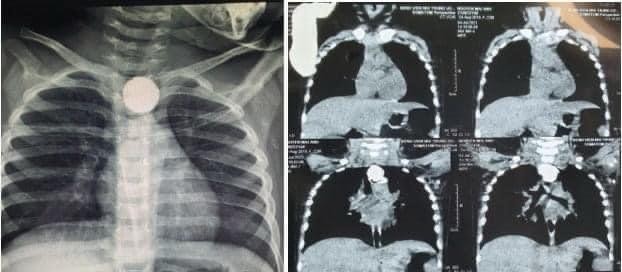

BS. Nguyễn Minh Khôi - Khoa Ngoại tổng hợp, Bệnh viện Nhi Trung ương - cho biết: Trẻ nhập viện trong tình trạng nhiễm trùng (sốt 39 độ, môi khô, lưỡi bẩn) và suy hô hấp (thở nhanh nông, rút lõm lồng ngực). Vì thế, các bác sĩ đã chỉ định chụp X-quang và chụp cắt lớp vi tính ngực (chụp CT) cho trẻ. Kết qủa, các bác sĩ phát hiện hình ảnh dị vật cản quang hình tròn nằm tại thực quản ngực của trẻ. Nếu không được phẫu thuật kịp thời thì tình trạng nhiễm trùng sẽ lan rộng, áp-xe trung thất, nhiễm trùng huyết gây nguy hiểm đến tính mạng. Các bác sĩ đã ổn định huyết động cho bé, hỗ trợ hô hấp bằng oxy mask, dùng kháng sinh và chỉ định phẫu thuật nội soi tiêu hoá kiểm tra và lấy dị vật.

| Hình ảnh chụp Xquang của bệnh nhi (Ảnh - BVCC) |

Trong quá trình nội soi, các bác sĩ đã tìm thấy dị vật viên pin dạng cúc áo đường kính 2,5cm tại thực quản ngực, cách cung răng 14cm và được gắp bằng dụng cụ nội soi. Sau khi gắp dị vật, các bác sĩ phát hiện thành thực quản và khí quản của bé bị loét thủng tạo thành một đường rò kích thước 2cm, bờ viêm nề chảy máu. Bệnh nhi được chẩn đoán rò khí thực quản do dị vật tiêu hoá và được đặt ống nội khí quản và chuyển đến Khoa Hồi sức tích cực ngoại khoa.